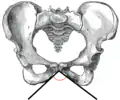

![]() حوض الأنثى (ويشار إلى القوس العانية) | |